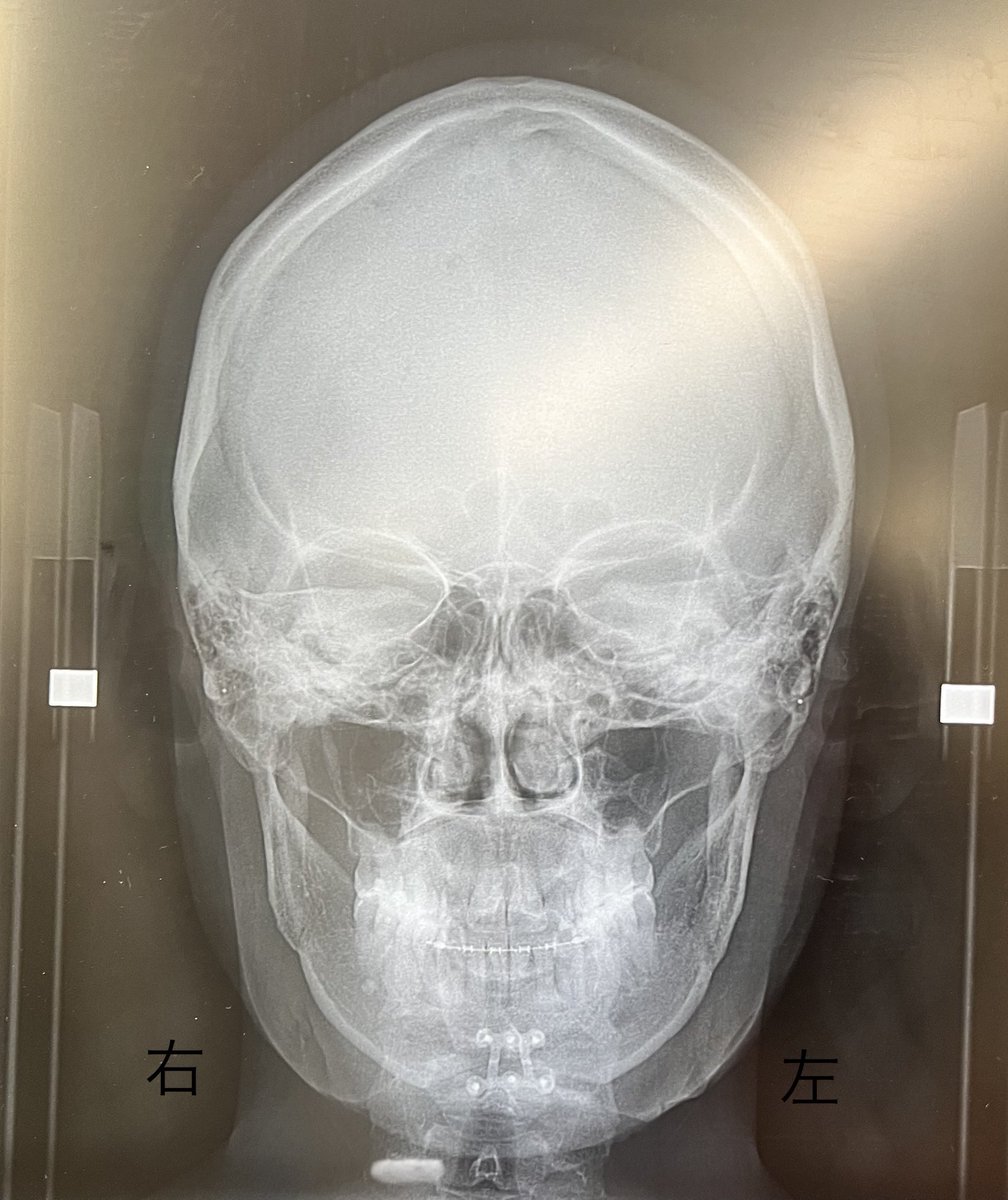

この左右の顎の歪みおかしくね?🥲 執刀医に連絡してもらってあとで説明してもらう🥺 右のが腫れてるとかそういうことなのかなぁ😭不安で泣きそう😭

この左右の顎の歪みおかしくね?🥲

執刀医に連絡してもらってあとで説明してもらう🥺

右のが腫れてるとかそういうことなのかなぁ😭不安で泣きそう😭

執刀医の診察 顎の左右の歪みについて、 まだ腫れてるからなんともだけど、骨の形は綺麗だし、そんなに心配することない なんなら顎が長い右側の方が、骨だけ見ると短くなってるくらいだよーとのこと 不安は残るけど、ここ数日の鬱解消してくれた...😂骨ばっか載せてすみません

執刀医の診察

顎の左右の歪みについて、

まだ腫れてるからなんともだけど、骨の形は綺麗だし、そんなに心配することない

なんなら顎が長い右側の方が、骨だけ見ると短くなってるくらいだよーとのこと

不安は残るけど、ここ数日の鬱解消してくれた...😂骨ばっか載せてすみません